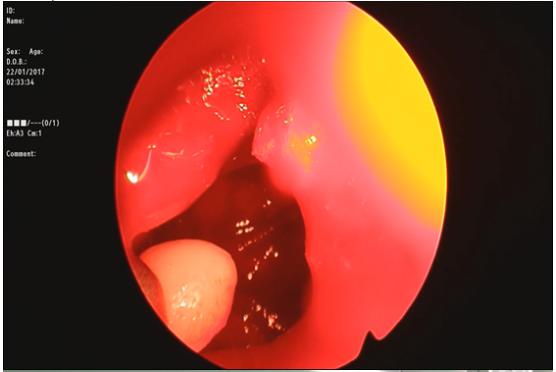

2017-02-08 00:00 2017年1月22日, 我院耳鼻咽喉科张民、谭韵主治医师顺利完成首例“鼻内镜下泪前隐窝入路上颌窦骨瘤切除术”,成功为一名右侧上颌窦骨瘤患者进行了手术治疗。

本例患者骨瘤位于上颌窦前下壁外侧,传统的FESS手术难以清除。此次进行的泪前隐窝进路手术由下鼻甲前端切开粘膜后经鼻泪管前端进入上颌窦,首先解剖并保护了鼻泪管,既保证了内窥镜手术创伤小、无可见切口,不影响面容,恢复快的优点,又保证了手术视野的清晰,患者术后3天手术切口已完全愈合,出院恢复。目前我市仅有西南医院、重医附一院、大坪医院等少数几家医院有能力开展。